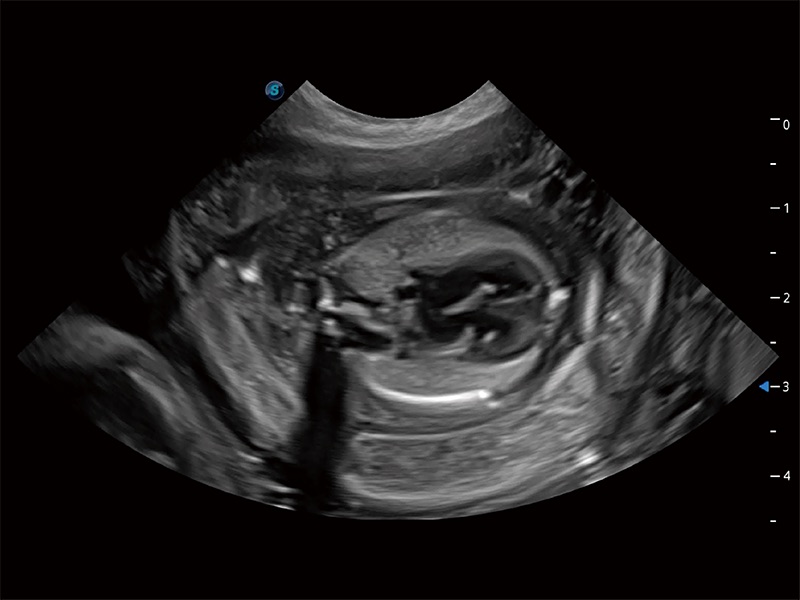

動(dòng)物是人類最親密的朋友和最值得信賴的伙伴。開立醫(yī)療也一直致力于探索動(dòng)物專用的超聲影像解決方案。全新推出的ProPet系列,是開立在動(dòng)物超聲影像智能化、專業(yè)化、精準(zhǔn)化的一次跨越式革新。動(dòng)物不能用言語(yǔ)來(lái)表述自己的不適,通過(guò)超聲影像,ProPet系列搭建了動(dòng)物醫(yī)生與不同物種溝通的“橋梁”,為動(dòng)物醫(yī)生注入了“治愈之力”。 ProPet 80 是開立醫(yī)療匠心打造的一款高端動(dòng)物專用彩超,采用性能卓越的全新硬件架構(gòu),極大提升超聲系統(tǒng)的運(yùn)行效率和數(shù)據(jù)處理能力,幫助動(dòng)物醫(yī)生從容應(yīng)對(duì)日益增多的挑戰(zhàn)性病例和日益多樣化的臨床需求。

高性能和先進(jìn)的臨床應(yīng)用工具可以為動(dòng)物醫(yī)生提供臨床信心。ProPet 80 搭載了先進(jìn)的腹部和淺表應(yīng)用工具,幫助醫(yī)生在日常臨床實(shí)踐中發(fā)揮前所未有的作用。

ProPet 80 全新的動(dòng)物超聲智能軟件和豐富的探頭群,為動(dòng)物醫(yī)生提供了高清晰度和精細(xì)分辨率的圖像,無(wú)論在寵物、馬科、畜牧還是實(shí)驗(yàn)室動(dòng)物等應(yīng)用中都可以輕松應(yīng)對(duì),為您的日常工作帶來(lái)滿意的體驗(yàn)。